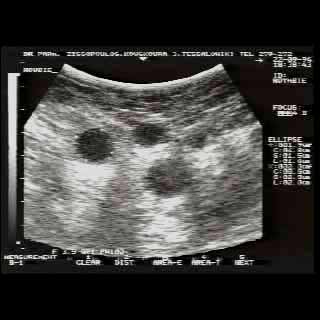

Η κλινικο-υπερηχογραφική διερεύνηση του μαστού είναι μία ακίνδυνη και πολύ αποτελεσματική μέθοδος εντόπισης εστιακών ευρημάτων.

Οι απεικονίσεις των περιστατικών που επιδεικνύονται παρακάτω, έγιναν με κυρτές κεφαλές 3,5 και 5 ΜΗΖ, προκειμένου να φανεί, ότι και με τον εξοπλισμό αυτό, που σιγά-σιγά διαθέτουν όλο και περισσότερα ιατρεία, είμαστε σε θέση να έχουμε ικανοποιητικά αποτελέσματα.